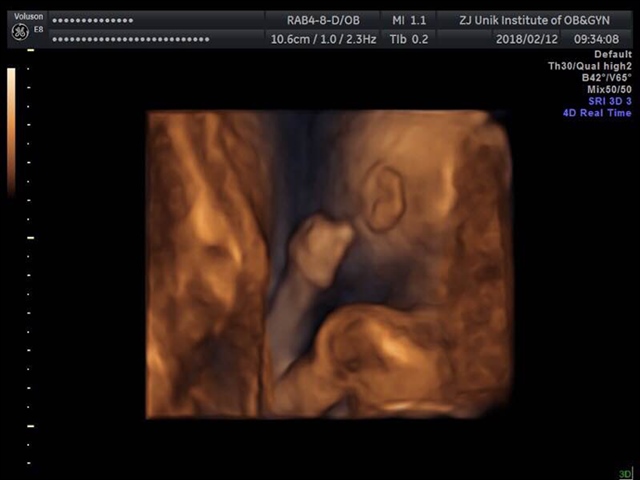

孕13周+1天

女孩

徐雨雨[帖主]:男孩